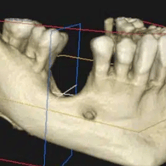

Atrofia ósea alveolar

La atrofia ósea alveolar es la pérdida de hueso en la mandíbula o el maxilar debido a la ausencia prolongada de dientes.

Los pacientes pueden notar que sus encías están hundidas y que las dentaduras no encajan bien.

El tratamiento puede incluir injertos óseos para preparar el sitio para la colocación de implantes.

Falta de hueso para implantes

La falta de hueso suficiente para la colocación de implantes puede ser una barrera para el tratamiento.

Los pacientes pueden ser informados de que no tienen suficiente hueso en la mandíbula o el maxilar para soportar un implante.

El tratamiento incluye técnicas de regeneración ósea, como injertos óseos, para aumentar el volumen óseo.